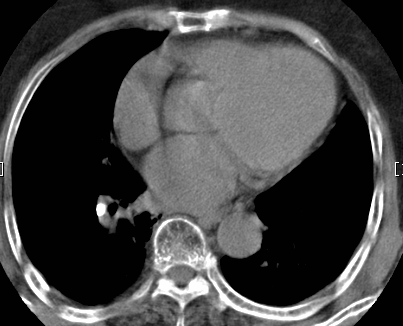

标题: CT26680:肺部右下肺静脉干结节的界定 [打印本页]

标题: CT26680:肺部右下肺静脉干结节的界定

考虑1、周围型肺癌,2肺静脉畸形,前者可能大,建议增强检查。

考虑1、周围型肺癌,2肺静脉畸形,前者可能大,建议增强检查。支持!

中心型肺癌,纤支镜可帮助明确。